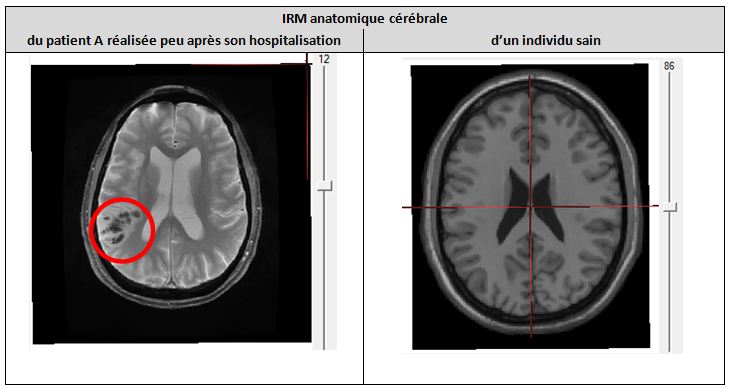

Activité pédagogique IRM médullaire + IRM cérébral et motricité

Figures et documents activité IRM médullaire + cérébral et motricité

Capture production partie 1 TP motricite.JPG